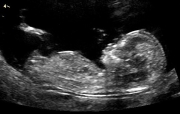

Ahoj, jmenuju se Jana a čekáme s přítelem Jirkou naše první mimčo :-) Mělo by se narodit 24.12. 2008, takže se už těšíme na opravdového Ježíška :-) Máme nachystaná 2 jména: Bětka a Hubert *:-) Fotky z UZ, které tady můžete vidět jsou z 8., 13. a z 29. týdne těhu :-)